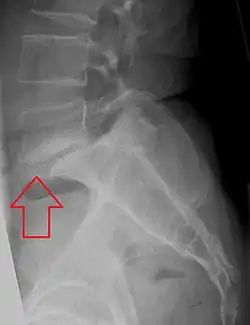

![]() | |

| X-ray of the lateral lumbar spine with a grade III anterolisthesis at the L5-S1 level | |

Spondylolisthesis is graded based upon the degree of slippage of one vertebral body relative to the subsequent adjacent vertebral body.[6] Spondylolisthesis is classified as one of the six major etiologies: degenerative, traumatic, dysplastic, isthmic, pathologic, or post-surgical.[7] Spondylolisthesis most commonly occurs in the lumbar spine, primarily at the L5-S1 level, with the L5 vertebral body anteriorly translating over the S1 vertebral body.[7]